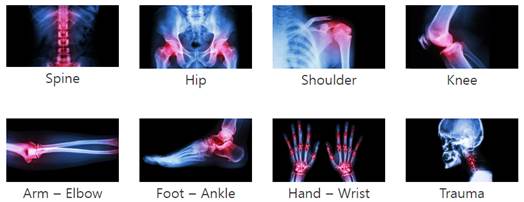

가장 대표적인 정형외과 협회는 호주 정형외과 의사 협회(Australian Society of Orthopaedic Surgeons, ASOS)로 해당 기관에는 호주 내 대부분의 정형외과 의사들이 등록돼 있으며 의사 각각의 전문 분야를 등록하도록 해 관리하고 있다. 분류된 전문 분야 카테코리를 보면 엉덩이(Hip), 어깨(Shoulder), 척추(Spine), 손·손목(Hand/Wrist), 무릎(Knee), 발·발목(Foot/Ankle), 팔꿈치·팔(Elbow/Arm), 트라우마(Trauma) 등 총 8개로 구분돼 있다.

호주 정형외과의사협회 내 전문분야별 카테고리 구분

자료: ASOS 홈페이지